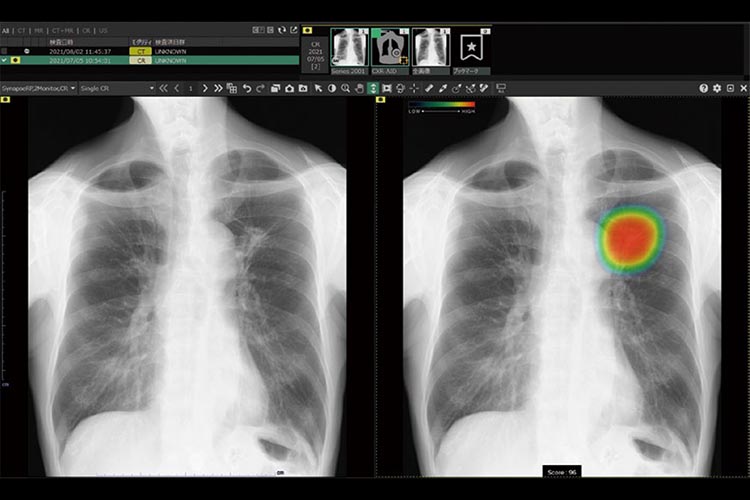

胸部レントゲンAI診断システム「CXR-AID」

特徴.AIと医師のダブルチェックによる見落とし防止

AI技術を活用し、撮影した胸部単純X線(胸部レントゲン)画像を自動解析。

異常が疑われる領域を検出しマーキングし、その領域を医師が再確認することで、見落し防止を支援します。